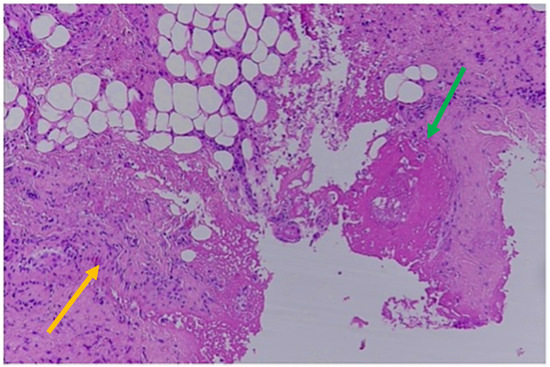

The SDHs showed histological findings consistent with subacute hemorrhages older than 5 days but less than a week, as represented by the formation of granulation tissue with associated breakdown of erythrocytes and some siderophages. A thin layer of fibroblasts was observed between the dura and the clot, and the latter was invaded by new capillary blood vessels [34]. Intense edema was also present based in large pericellular and perivascular empty spaces (Figure 4).

Figure 4.

Histological findings of subacute SDHs > 5 days old: thin layer of fibroblasts between the dura and the clot (yellow arrow); granulation tissue; siderophages; breakdown of erythrocytes (yellow arrow; Hematoxylin & Eosin).